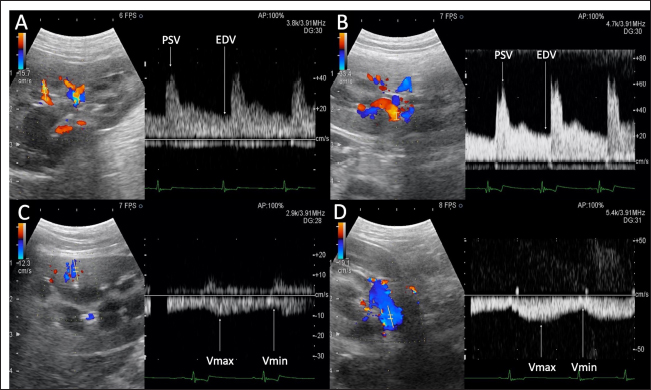

Ultrasonography

Fig. 1. Renal blood flow waveform on pulsed Doppler ultrasonography. Flow waveform of the renal interlobar artery (A), renal artery (B), renal interlobar vein (C), and renal vein (D). The arterial blood flow waveform peaks sharply and quickly during systole (PSV), after which the flow velocity gradually slows to a minimum at end-diastole (EDV). The venous blood flow waveform is continuous, with the fastest waveform (Vmax), followed by a gradual slowing to a minimum (Vmin). EDV, end-diastolic velocity; PSV, peak systolic velocity; Vmax, maximum venous flow velocity; Vmin, minimum venous flow velocity.